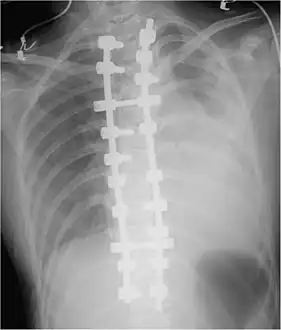

Chest X-ray

-

Development of hemothorax following lung lesion biopsy -

Showing a massive left-sided hemothorax -

Right showing a massive right hemothorax

A chest X-ray is the most common technique used to diagnosis a hemothorax.[23] X-rays should ideally be taken in an upright position (an erect chest X-ray), but may be performed with the person lying on their back (supine) if an erect chest X-ray is not feasible. On an erect chest X-ray, a hemothorax is suggested by blunting of the costophrenic angle or partial or complete opacification of the affected half of the thorax. On a supine film the blood tends to layer in the pleural space, but can be appreciated as a haziness of one half of the thorax relative to the other.[5] A small hemothorax may be missed on a chest X-ray as several hundred milliliters of blood can be hidden by the diaphragm and abdominal viscera on an erect film. Supine X-rays are even less sensitive and as much as one liter of blood can be missed on a supine film.[24]